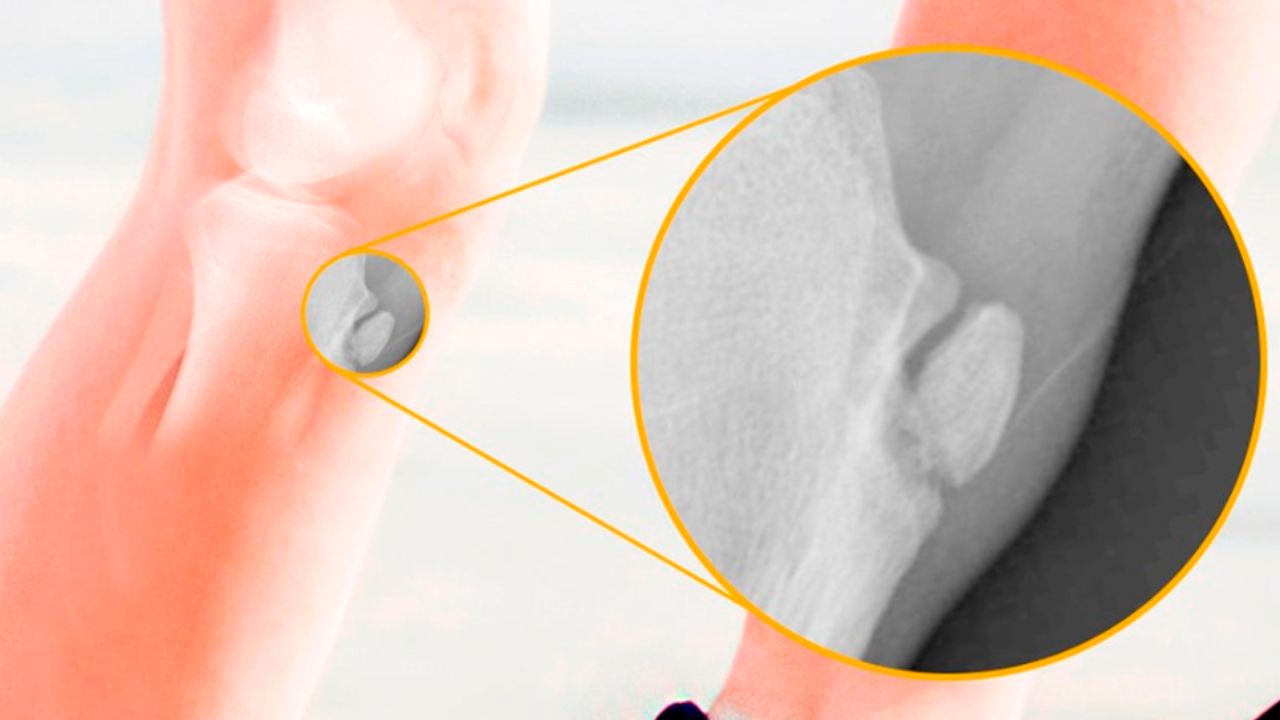

O diagnóstico é simples e realizado pelo ortopedista através do exame físico e da história clínica do paciente. O raio-x pode ser solicitado para descartar outras patologias, como fraturas ou tumores ósseos, e geralmente mostra a irregularidade ou fragmentação na tuberosidade da tíbia característica da síndrome. É importante tranquilizar os pais e o paciente de que se trata de uma condição autolimitada, ou seja, que tende a se resolver sozinha conforme o esqueleto amadurece.